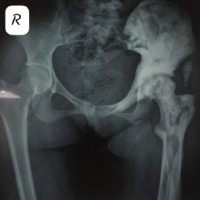

We report a 65-year-old woman (IP No2309804) with 2 years of bilateral knee pain and swelling, worsened by activity. She experienced night pain, cracking sounds, and reduced mobility due to advanced bilateral osteoarthritis (stage 4) with varus and fixed flexion deformity (FFD) (Fig. 1).Sequential bilateral robotic-assisted TKA was recommended.